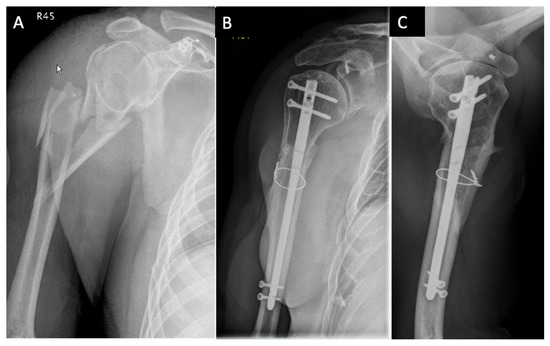

| Case | Age, years | Sex | Neer | AO/OTA Proximal | AO/OTA Metaphyseal | Stedtfeld | Garnavos/ Lasanianos | Implant/ Metaphyseal Fixation | FU, Months/ CMS-K | Revision |

|---|---|---|---|---|---|---|---|---|---|---|

| 1 | 65 | M | IV | 11-B1 | 12-C2 | D4 | Combined | Retrograde nail | 48/83 | - |

| 2 | 74 | F | III | 11-A3 | 12-C3 | A2 | Extended | T-nail | 97/51 | Metaphyseal lack of fixation, material removal |

| 3 | 68 | F | IV | 11-B1 | 12-C1 | D2 | Extended | T-nail | 32/71 | Metaphyseal lack of fixation, change to plate |

| 4 | 43 | M | IV | 11-B1 | 12-C3 | D3 | Extended | T-nail/cerclage | 92/77 | - |

| 5 | 74 | F | V | 11-B2 | 12-C1 | B1-3 | Extended | T-nail/screw | 52/64 | - |

| 6 | 65 | M | III | 11-A2 | 12-A1 | A2 | Extended | T-nail/screw | 60/62 | - |

| 7 | 75 | F | III | 11-A2 | 12-C1 | C3 | Extended | T-nail | 91/64 | - |

| 8 | 72 | F | VI | 11-C3 | 12-C3 | D3 | Extended | T-nail/screw | 55/68 | Metaphyseal lack of fixation, inverse prothesis |

| 9 | 55 | F | III | 11-A2 | 12-C1 | B2-1 | Extended | T-nail | 70/99 | - |

| 10 | 67 | F | III | 11-A2 | 12-C1 | C2 | Extended | Locking plate/ cerclage, lag screw | 63/99 | - |

| 11 | 37 | F | IV | 11-B1 | 12-C1 | D3 | Extended | T-nail/screw | 34/86 | - |

| 12 | 50 | F | III | 11-A2 | 12-C1 | C4 | Combined | T-nail/cerclage | 49/97 | - |

| 13 | 76 | F | V | 11-C2 | 12-C2 | D4 | Combined | Locking plate/ lag screw | 58/65 | - |

| 14 | 71 | M | IV | 11-B1 | 12-C1 | D4 | Extended | T-nail/screw | 15/38 | Loss of reduction, proximal nail displacement, material removal |

| 15 | 70 | F | IV | 11-B1 | 12-C2 | D4 | Combined | T-nail/cerclage | 15/70 | - |

| 16 | 23 | M | IV | 11-B2 | 12-C2 | D4 | Combined | Locking plate/ plate | 35/99 | - |

| 17 | 46 | F | V | 11-C2 | 12-C3 | B1-3 | Extended | Locking plate/ lag screw | 57/100 | - |

| 18 | 76 | F | III | 11-A2 | 12-C1 | C2 | Extended | T-nail | 12/72 | - |

| 19 | 53 | F | III | 11-A3 | 12-C3 | C3 | Extended | T-nail/screw | 12/48 | Metaphyseal lack of fixation, change to plate |

| 20 | 53 | F | IV | 11-B1 | 12-A1 | B2-3 | Extended | T-nail | 12/74 | - |

| 21 | 51 | F | IV | 11-B1 | 12-C1 | D2 | Extended | Locking plate/ lag screw | 37/89 | - |

| 22 | 49 | M | V | 11-C2 | 12-C3 | D2 | Combined | Locking plate/ plate | 61/50 | - |

| 23 | 48 | F | V | 11-C2 | 12-C3 | B1-3 | Extended | Locking plate | 45/84 | - |

| 24 | 68 | M | IV | 11-B1 | 12-C1 | B1-2 | Extended | Locking plate/ lag screw | 12/45 | Metaphyseal lack of fixation, pseudarthrosis |

| 25 | 74 | F | III | 11-C1 | 12-C3 | C3 | Extended | Locking plate/ cerclage | 13/62 | - |